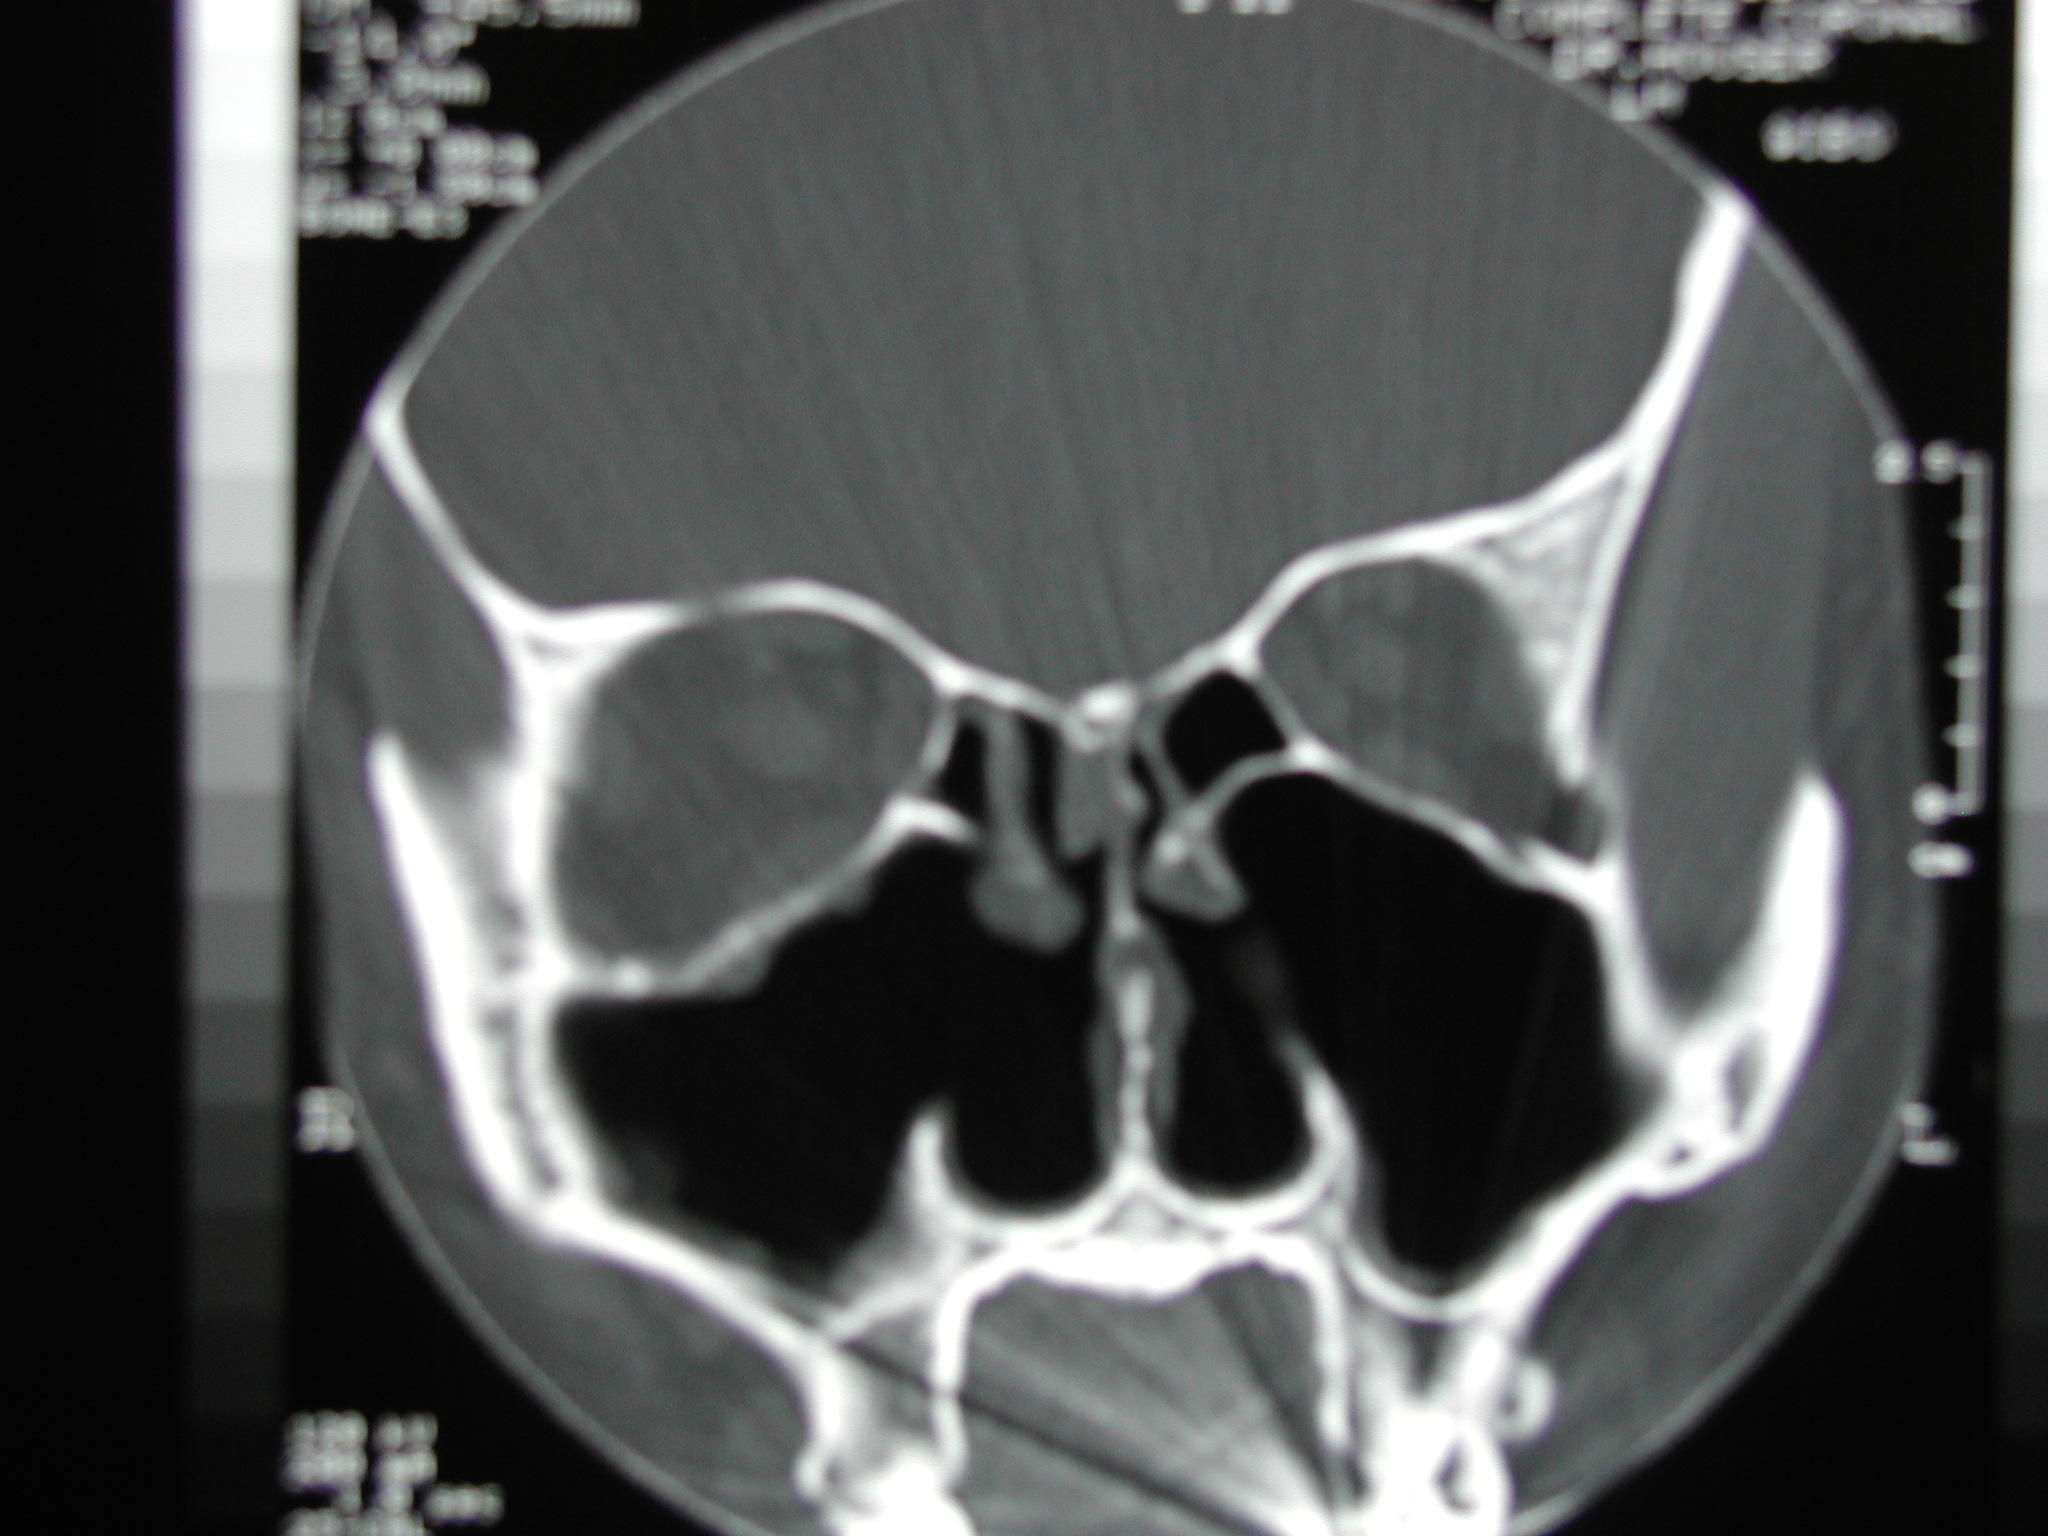

The "Empty Nose Syndrome" is a term coined by Eugene Kern, MD, at the Mayo Clinic.  It refers to the fact that a patient's CT scan looks empty, or devoid of normal tissue, following  nasal surgery, specifically turbinate excision.  The CT scan below depicts a typical view of a patient experiencing the symptoms of empty nose syndrome.

The CT above depicts a patient with empty nose syndrome after inferior turbinate resection.